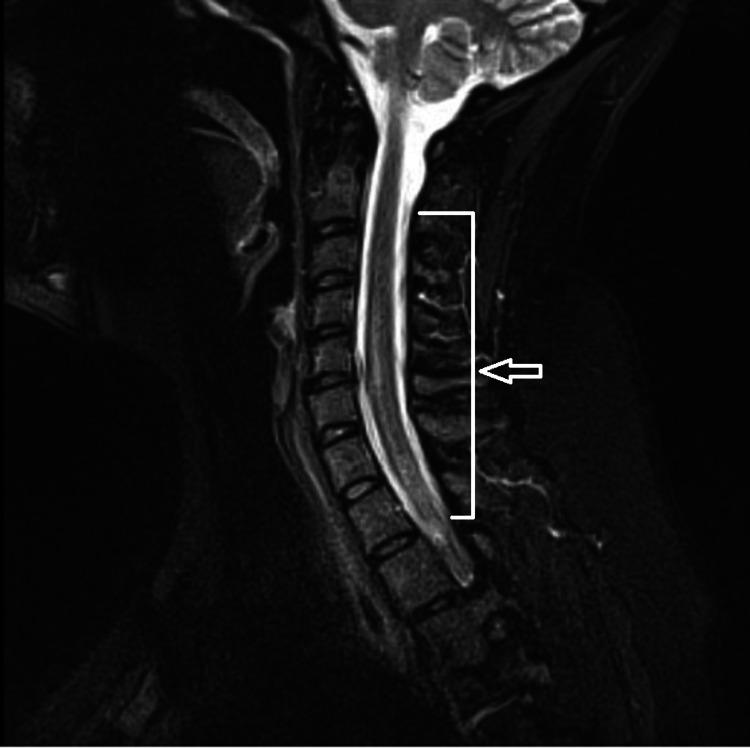

While mass immunization against coronavirus disease 2019 (COVID-19) rolls out around the globe, safety concerns and adverse events that need prompt evaluation are also emerging. We report a case of transverse myelitis and Bell's palsy after receiving Johnson and Johnson COVID-19 vaccination under the emergency use authorization in a healthy young woman with no past medical history. Other possible etiologies of her symptoms were ruled out, and she was treated successfully with steroids and plasma exchange.

在全球范围内开展针对2019冠状病毒病(COVID-19)的大规模免疫接种之际,需要迅速评估的安全问题和不良事件也不断出现。我们报告了一例在紧急使用授权下接种强生公司COVID-19疫苗后发生横贯性脊髓炎和贝尔麻痹的病例,患者为一名既往无病史的健康年轻女性。其症状的其他可能病因已被排除,她接受了类固醇和血浆置换治疗并成功康复。